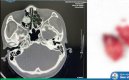

Tại đây, các bác sĩ chỉ định chụp cộng hưởng từ sọ não (MRI). Kết quả cho thấy khối u màng não đường kính khoảng 40mm, nằm sâu ở nền sọ hố thái dương phải, chèn ép não và xâm lấn động mạch não giữa phải.

Trong trường hợp này người bệnh có khối u não kích thước lớn sát nền sọ vị trí hố thái dương phải, khối u có xâm lấn động mạch não giữa phải (nếu gây tổn thương động mạch não giữa có thể khiến người bệnh liệt lửa người thậm chí đe dọa đến tính mạng.